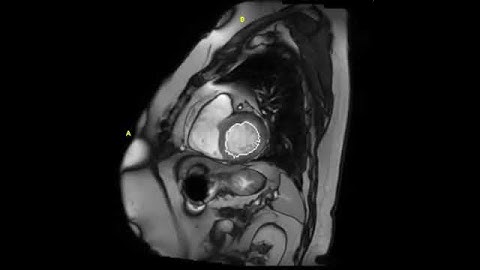

Revealing myocardial microstructure within vivo cardiac DT-MRI